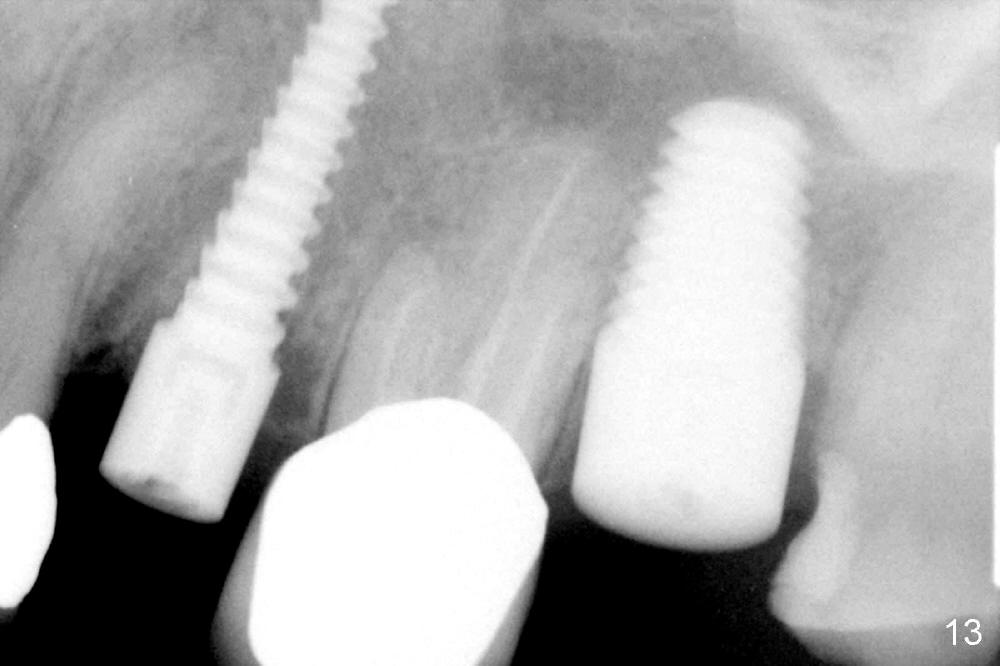

A 66-year-old lady requests restoring a broken tooth (Fig.1). Osteotomy is initiated in a thin septum (Fig.2 (occlusal mirror view) S) by sectioning, drilling and tapping (Fig.3 T). When 7x17 mm tap is removed, the osteotomy is found to form basically in the middle of socket (Fig.4 O). The apical portion of three sockets (Fig.5: MB, P and DB (not labeled) is packed with mixture of autogenous bone and allograft. When a 7x14 mm implant is placed, there are buccal and lingual gaps (Fig.6 *). The latter are bone grafted again (Fig.8 *) and require a coverage. After placement of a 4x3 mm abutment (Fig.7,8 A), an immediate provisional is fabricated (Fig.9 tissue surface view) to cover the remaining sockets (Fig.10 (occlusal mirror view), 11 (buccal view)). The provisional is infra-occlusal, i.e., load-free (Fig.11). The buccal and lingual aspects of the socket are covered by fresh epithelium 8 days postop (Fig.12 <). The implant appears to have osteointegrated 4 months postop (Fig.13). The tooth #16 appears to have shifted mesially. It is difficult to prepare for #15 crown. Luckily the patient agrees to have it extracted because of persistent sensitivity after MO composite. The definitive crown at the site of #15 is cemented 6 months postop (Fig.14).